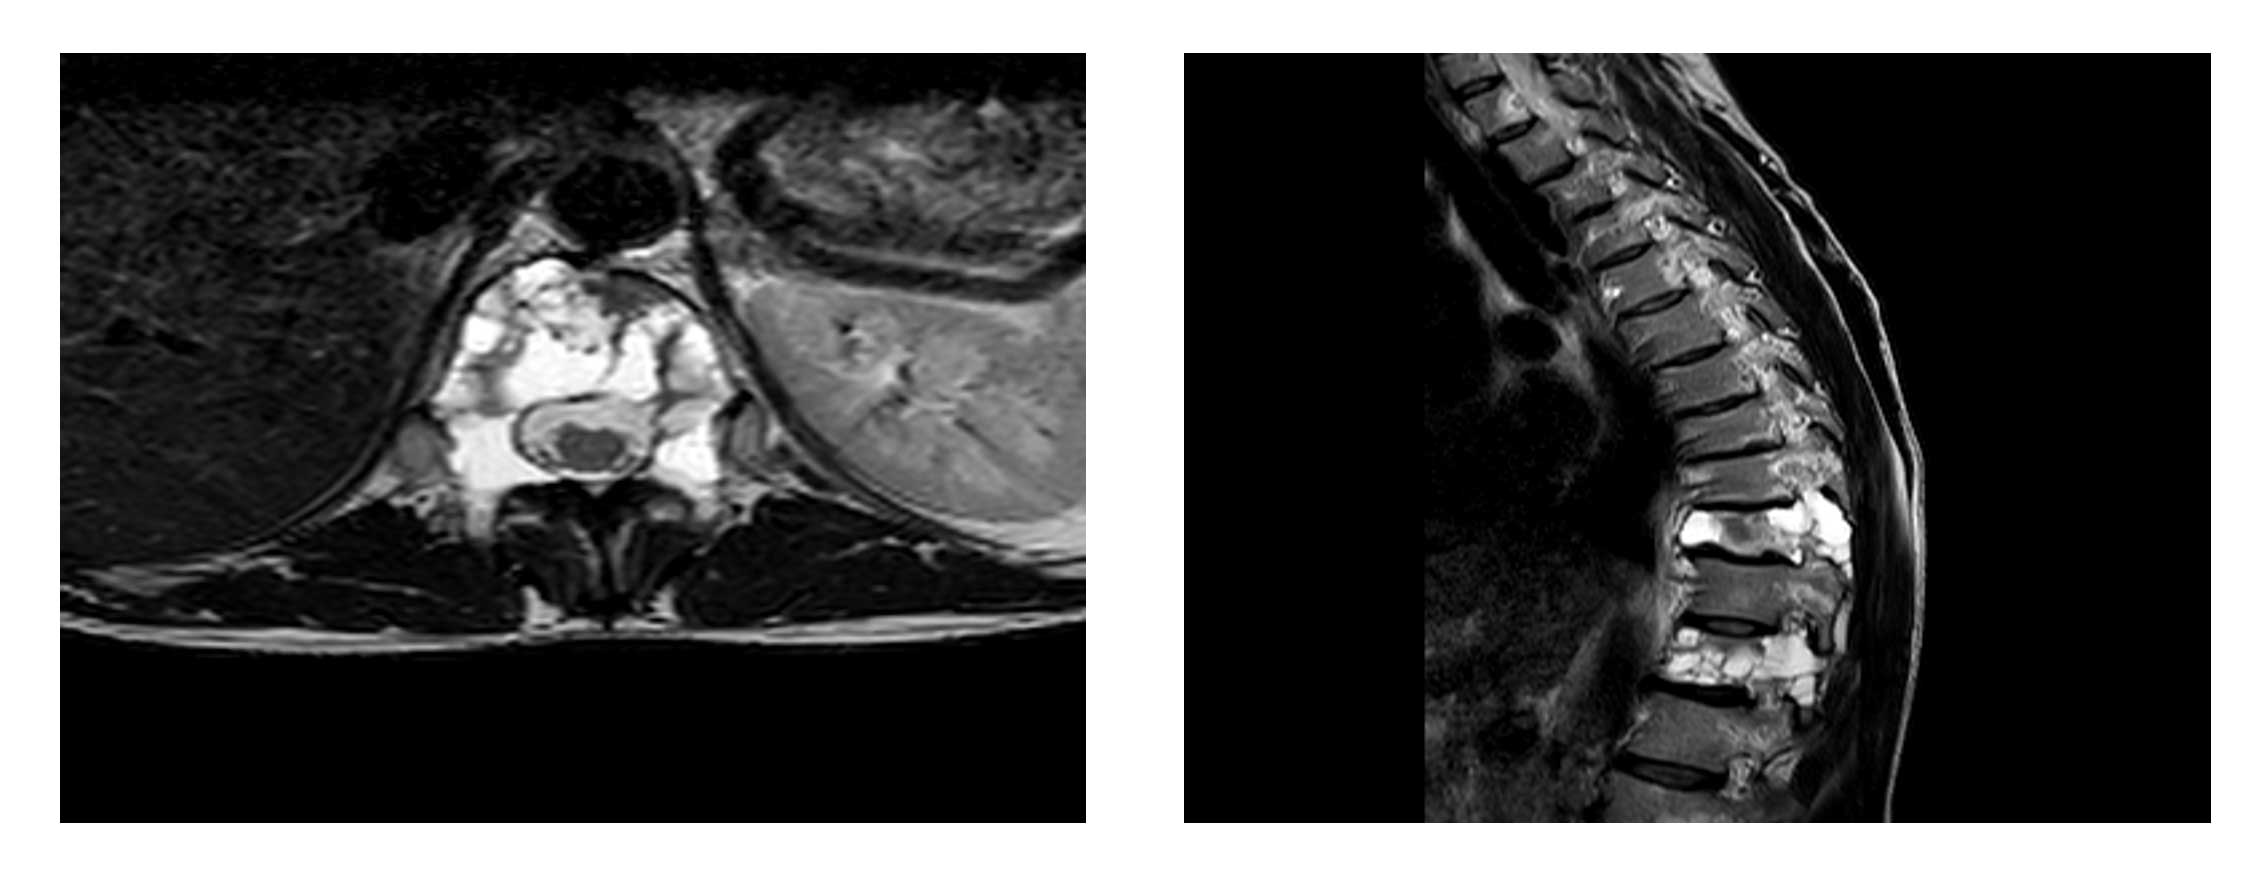

Ameliyat Öncesi: MR’da kemiğin içini tamamen dolduran kistik lezyon görülmekte.